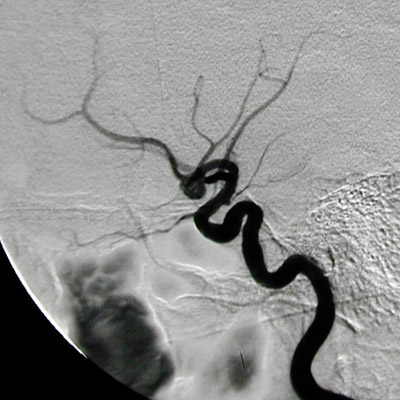

The cerebral angiogram above and below demonstrates a berry aneurysm involving the anterior communicating artery of the circle of Willis at the base of the brain.